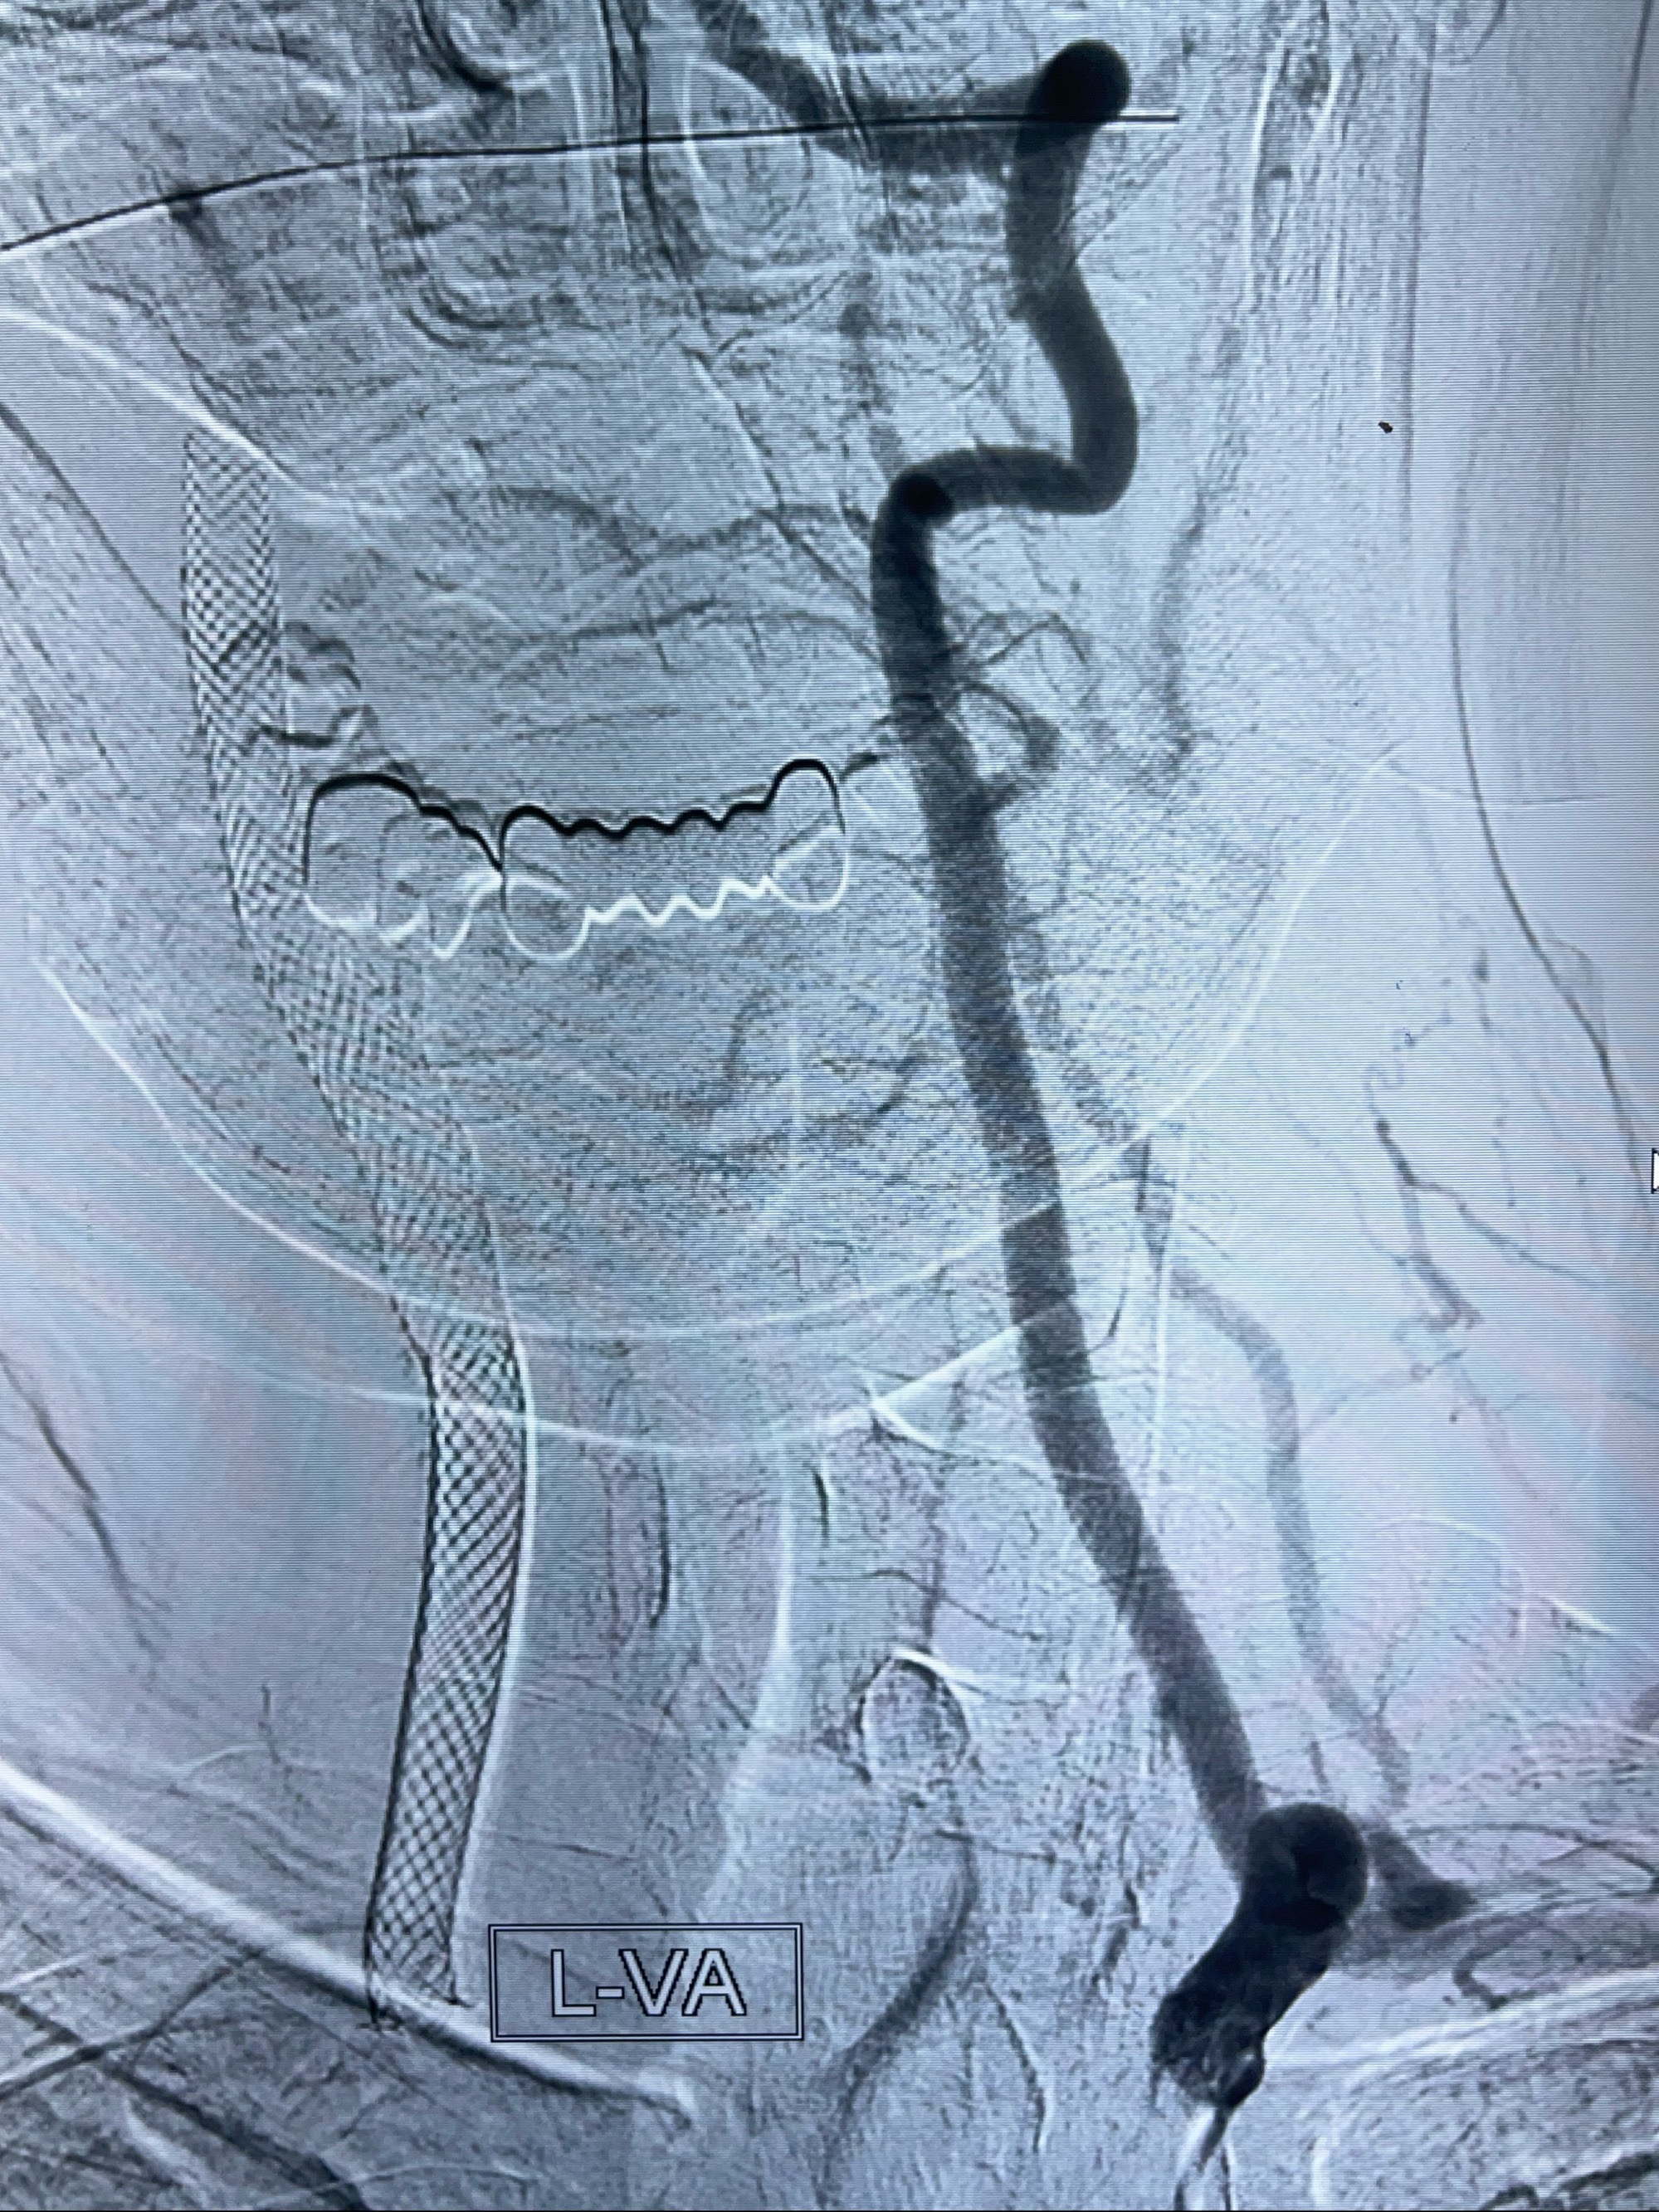

2023-07-10DSA:右侧颈内动脉岩骨段夹层伴中偏重度狭窄改变,左侧颈总动脉闭塞、右侧颈外动脉由右侧肋颈干甲颈干吻合代偿

箭头所示为颈内动脉岩骨段重度狭窄,结合MRI,考虑为肿瘤侵犯右侧颈内动脉

箭头以近至支架段管腔不规则狭窄

右侧椎动脉可见吻合代偿右侧颈外动脉

左侧颈总动脉起始段至分叉部闭塞,起始部呈现子弹头样改变

左侧椎动脉可见代偿显示左侧前循环